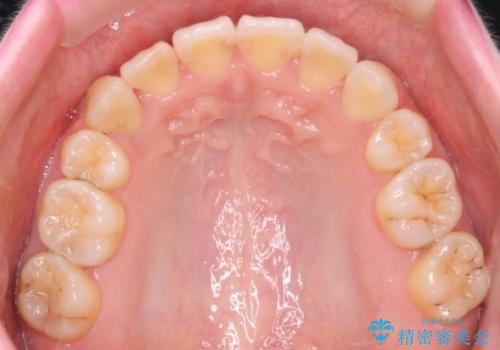

今回の場合も、ブリッジを除去して矯正後にセラミックブリッジを装着しました。

八重歯のワイヤーによる抜歯矯正 矯正治療と並行してセラミック治療も